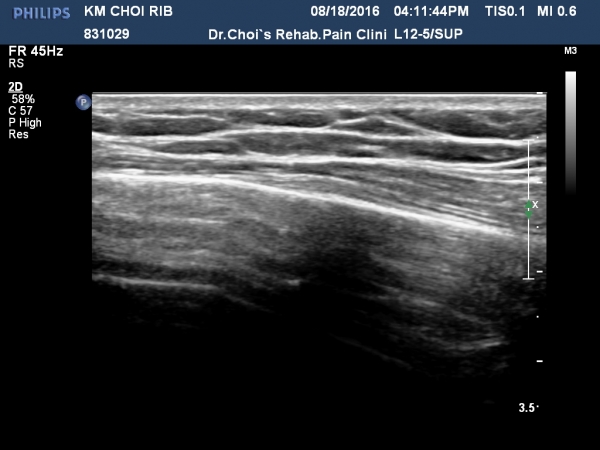

ÃÊÁø ½Ã °¥ºñ»À ÃÊÀ½ÆÄ°Ë»ç¿¡¼­ ÇÇÁú°ñ ¤·³à¼Ó¼º ¼Ò½ÇÀº º¸ÁöÁö ¾ÊÀ¸³ª

±æºñ»À Ç¥Ãþ¿¡ ±¹¼ÒÀûÀÎ ¿¬ºÎÁ¶Á÷ ºÎÁ¾ÀÌ °üÂûµÈ´Ù(»çÁø 1, 2, 3, 4).